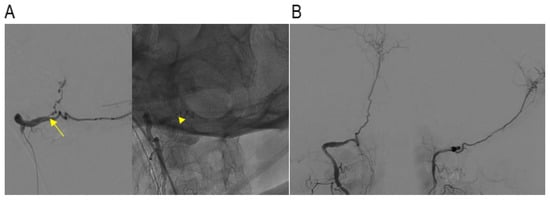

3.2.3. Endovascular Treatment